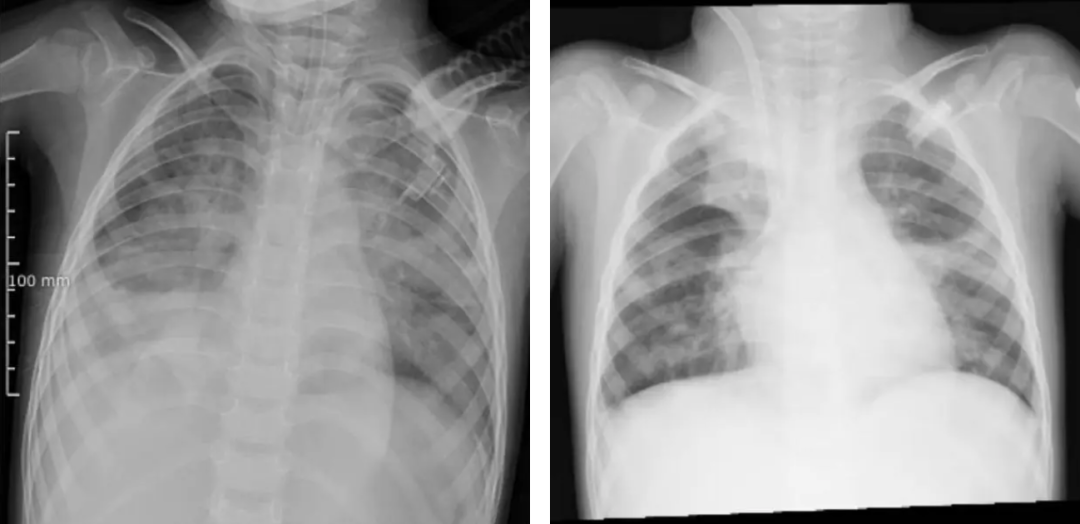

图源?河南省儿童医院(左图为ECMO上机前,肺部结构模糊,呈现“白肺”影像表现。右图为ECMO支持治疗5天后,肺部影像清晰度明显改善)